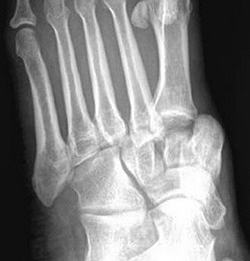

(Справа) У этого же пациента при рентгенографии голеностопного сустава в боковой проекции подтверждается наличие вывиха подтаранного сустава. Задняя суставная поверхность пяточной кости не сочленяется с соответствующей суставной поверхностью таранной кости. Кроме того, выявляется перелом латерального отростка таранной кости. Суставные поверхности таранно-ладьевидного сустава конгруэнтны. (Слева) При рентгенографии голеностопного сустава в передне-задней проекции определяется медиальный вывих подтаранного сустава. Задняя суставная поверхность таранной кости не сочленяется с соответствующей суставной поверхностью пяточной кости.

(Справа) У этого же пациента при рентгенографии голеностопного сустава в боковой проекции визуализируется вывих заднего и среднего отделов подтаранного сустава. Кроме того, выявляются переломы «задней лодыжки» и задней части тела таранной кости. Шейка таранной кости не повреждена. Наблюдается вывих таранно-ладьевидного сустава. (Слева) При рентгенографии голеностопного сустава в передне-задней проекции определяется вывих таранной кости. Ее головка ротирована латерально. Также выявляется перелом медиальной лодыжки.